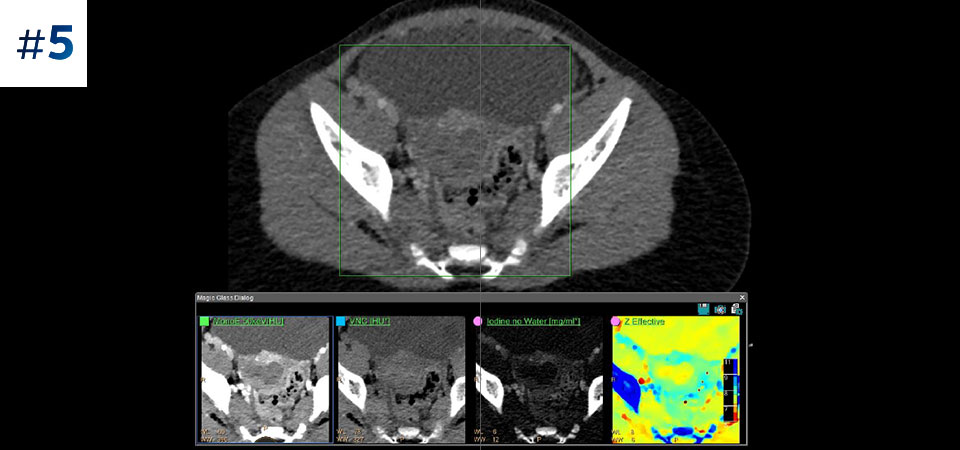

Vai oltre la TC convenzionale. Scopri come i risultati con diversi strati del detettore spettrale possono migliorare l'affidabilità diagnostica.

Osserva la differenza tra la TC basata su detettore spettrale e la TC convenzionale